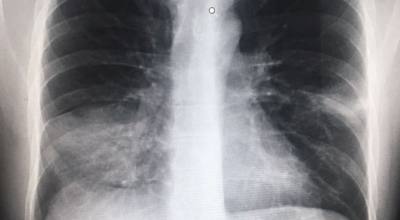

증상을 겪는 경우 배양 검사는 물론 X-ray 촬영 등을 통해 진단을 할 수 있어요. 필요한 경우 소변, 혈액, 혈청 검사, CT 등이 추가적으로 진행돼요.